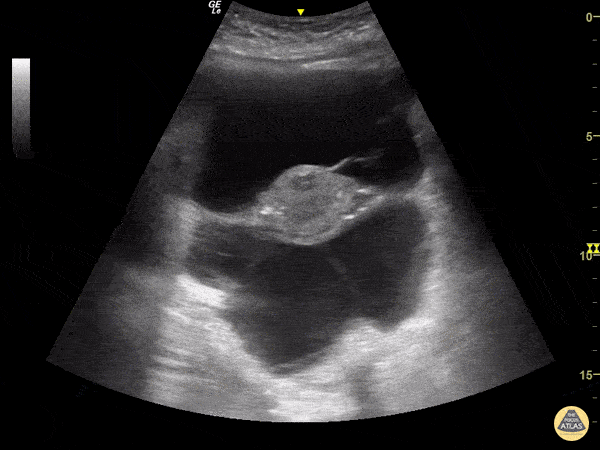

Bowel-GI - Large Volume Ascites on Transverse Pelvic View

A 64-year-old woman with hepatic cirrhosis presented to the emergency room with abdominal pain. An abdominal POCUS exam was performed showing significant ascites. In this transverse pelvic view one can appreciate the uterus floating in ascites. This image finding is also known as the "TIE Fighter Sign" in reference to the famous Starwars galactic empire ship. Image Courtesy of Dr. Renato Tambelli @RTambelli / @JediPocus